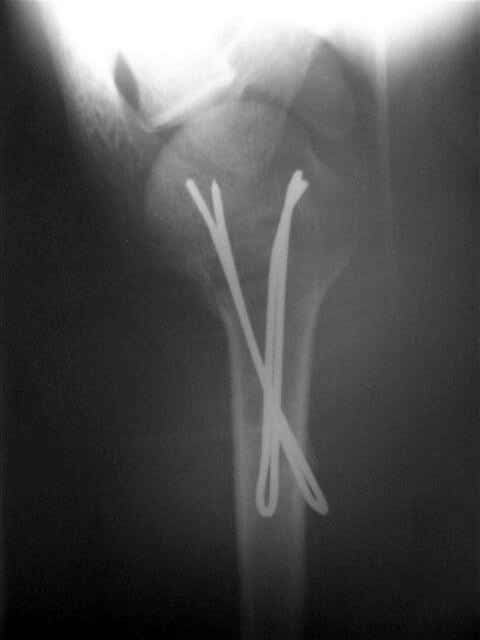

Сегодня взял больного повторно в операционную, не скажу, что повторная репозиция через неделю после первой попытки, была простая.

После удаления спиц попытался манипулировать отломками, но безуспешно, поэтому пришлось пользоваться периостальным элеватором, чтобы устранить смещение отломков и перепровести спицы. Проверил и перепроверил стабильность фиксации под ЭОПом, завтра Рг- будет готов, вот и поглядим....

Уважаемые коллеги,

Спасибо за участие в дискуссии -перелом шейки плеча, для себя я прояснил многие технические моменты...

Посылаю послеоперационные Рг граммы.

Поздравляю, получилось просто замечательно. Если можно, расскажи чуть подробнее, как делали - как вправляли, как вводили спицы, поворачивали ли их?

Спасибо за поздравления:-))

Я и сам доволен результатом. В предпоследнем письме я кратко описал ход операции - закрыто репонировать не удалось( 2 недели с момента травмы и 1 неделя после неудачной репозиции) после удаления пучков спиц, пришлось сделать - 2см разрез на уровне перелома и с помощью периостального элеватора (золотое правило механики) *одеть* головку на дистальный отломок.

Спицы проводил через старые отверстия, вращая пучок импактором- направителем при его введении в головку.